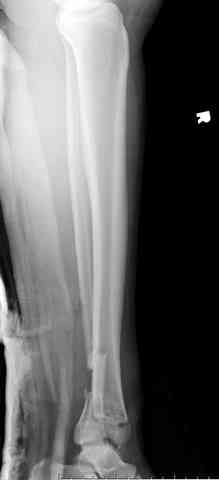

Снова приветствую вас, коллеги. К моменту вступления в обсуждение аксакалов, операция была, увы, выполнена(31.10.07.) Начали с доступа к наружной лодыжке, произвели ее фиксацию спицами, развернули кусок заднего края, наложили дистрактор, затем произвели дистракцию, фиксацию спицами дистального эпиметафиза б/бк,Рентгено-контроль. синтез наружной лодыжки 1/3пластиной. из двух коротких разрезов сформирован канал под медиальную тибиальную пластину LCP. Края ран ушиты без натяжения. Прочувствовать жесткость фиксации винтами с угловой стабильностью не удалось, поэтому дистрактор оставлен на энное время.

На представленных R-снимках не окончательный вид после остеосинтеза. Дистальная опора давила на стопу, пришлось ее сместить проксимально, в рез-те чего, она закрыла щель сустава, последние снимки не информативны.